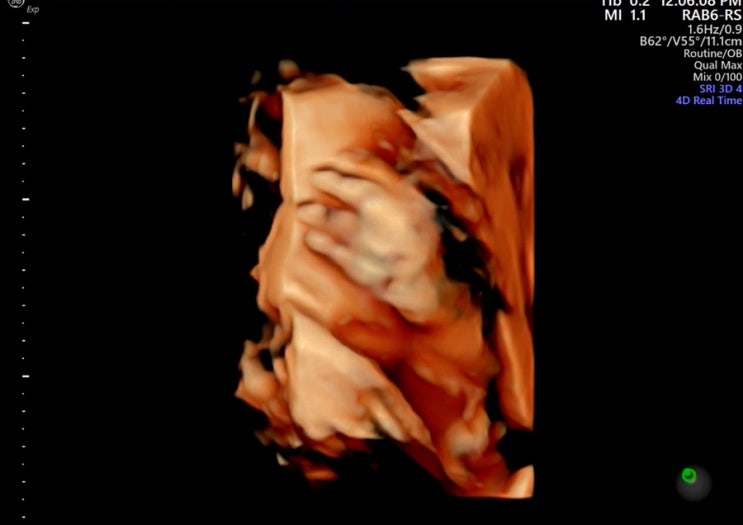

[임신일기 12] 임신 32주 증상 33주 정기검진

임신 32주차 되니까 배가 꽤 많이 무겁다! 조금 많이 걸으면 밤에 사타구니 아프고 많이 안 걸어도 기본적...